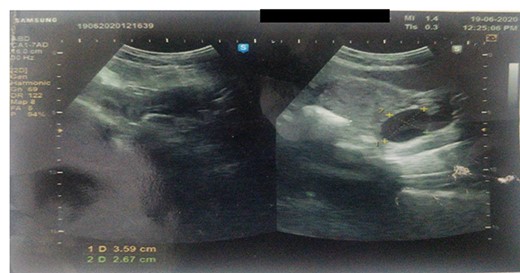

Ultrasound revealed a well-defined tubular cystic structure with clear contents in the right inguinal canal up to labia majora measuring 5cm × 3.5 cm × 5 cm (Fig. 1) with a volume of 50–60 ml. Color doppler revealed avascular cystic structure. The size and contents of the cyst are not increasing on the Valsalva maneuver.

Ultrasound showing a well-defined tubular cystic structure with clear contents in the right inguinal canal up to labia majora measuring 5 cm × 3.5 cm × 5 cm with a volume of 50–60 ml.